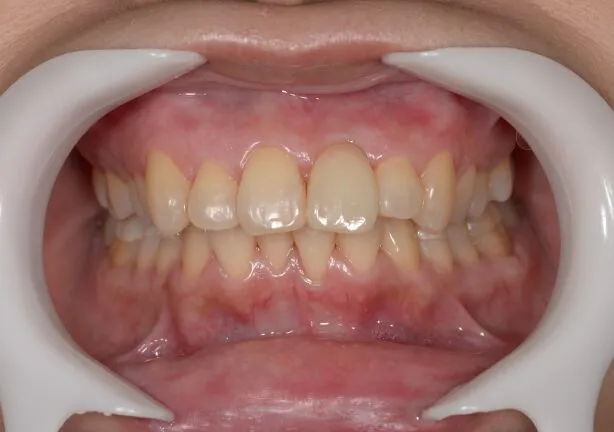

case2

After

治療内容 | 口腔内診査〜カウンセリング 歯周初期治療 仮歯にて噛む位置の再設定 インプラント埋入 仮歯にてインプラントを含めた噛む位置の決定 最終的な被せ物(ジルコニア)の型取り〜装着 |

---|---|

治療期間 | 1年半 |

治療回数 | 40回 |

リスク | リーニングにこない場合噛み合わせの確認ができないため装着していった人工物が割れてしまう可能性があるため、今後のメンテナンスが必須となる |

費用(税込) | 約¥2,860,000 |